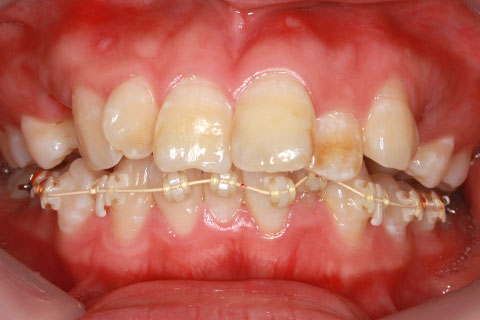

ハーフリンガル矯正3:上の歯のみ舌側矯正で治療(矯正期間24ヶ月)

治療前

治療中(開始直後)

治療中(開始半年後)

治療後

- 年齢・性別

- 25歳女性

- 治療期間

- 2年0ヶ月

- 抜歯

- 上下4番抜歯

- 治療費

- 110万円

- 治療内容

- 施術の副作用(リスク)

- 表側矯正と比較して、力学的な操作性が複雑なため、ボーイングエフェクトを起こしやすい。